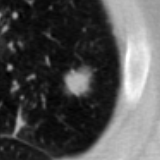

The current study focuses on lung nodule retrieval from a database of CT scans, where patches taken from CT slices of pulmonary nodules are to be mapped into an embedding. LIDC-IDRI [5] is a dataset of thoracic CT scans of 1,010 patients. All the scans were annotated by up to four radiologists, where each one identified, segmented and evaluated separately the lung nodules of a diameter above . Their evaluation also included ratings for a set of 9 characteristics: Subtlety, Internal structure, Calcification, Sphericity, Margin, Lobulation, Spiculation, Texture and Malignancy. The rating system was based on a discrete score of 1-5. Four examples of nodule patches are illustrated in Figure 2: 2 benign (a, b) and 2 malignant (c, d). A rounded vector of the mean rating is bellow each nodule, with the characteristics ordered according to the listing above. The most prominent difference between a and b is the calcification: 3 (solid) and 6 (absent) accordingly. d compared to c has a more defined margin, is more lobulated, but less spiculated. The malignancy score is used to define malignancy classes: score of 1-2 is benign, score of 3 is unknown, and a score of 4-5 is malignant.

(a) Benign

3, 1, 3, 3, 4, 3, 1, 5, 1

(b) Benign

3, 1, 6, 5, 5, 1, 1, 5, 2

(c) Malignant

5, 1, 6, 3, 3, 4, 1, 5, 5

(d) Malignant

4, 1, 6, 3, 4, 2, 2, 5, 4